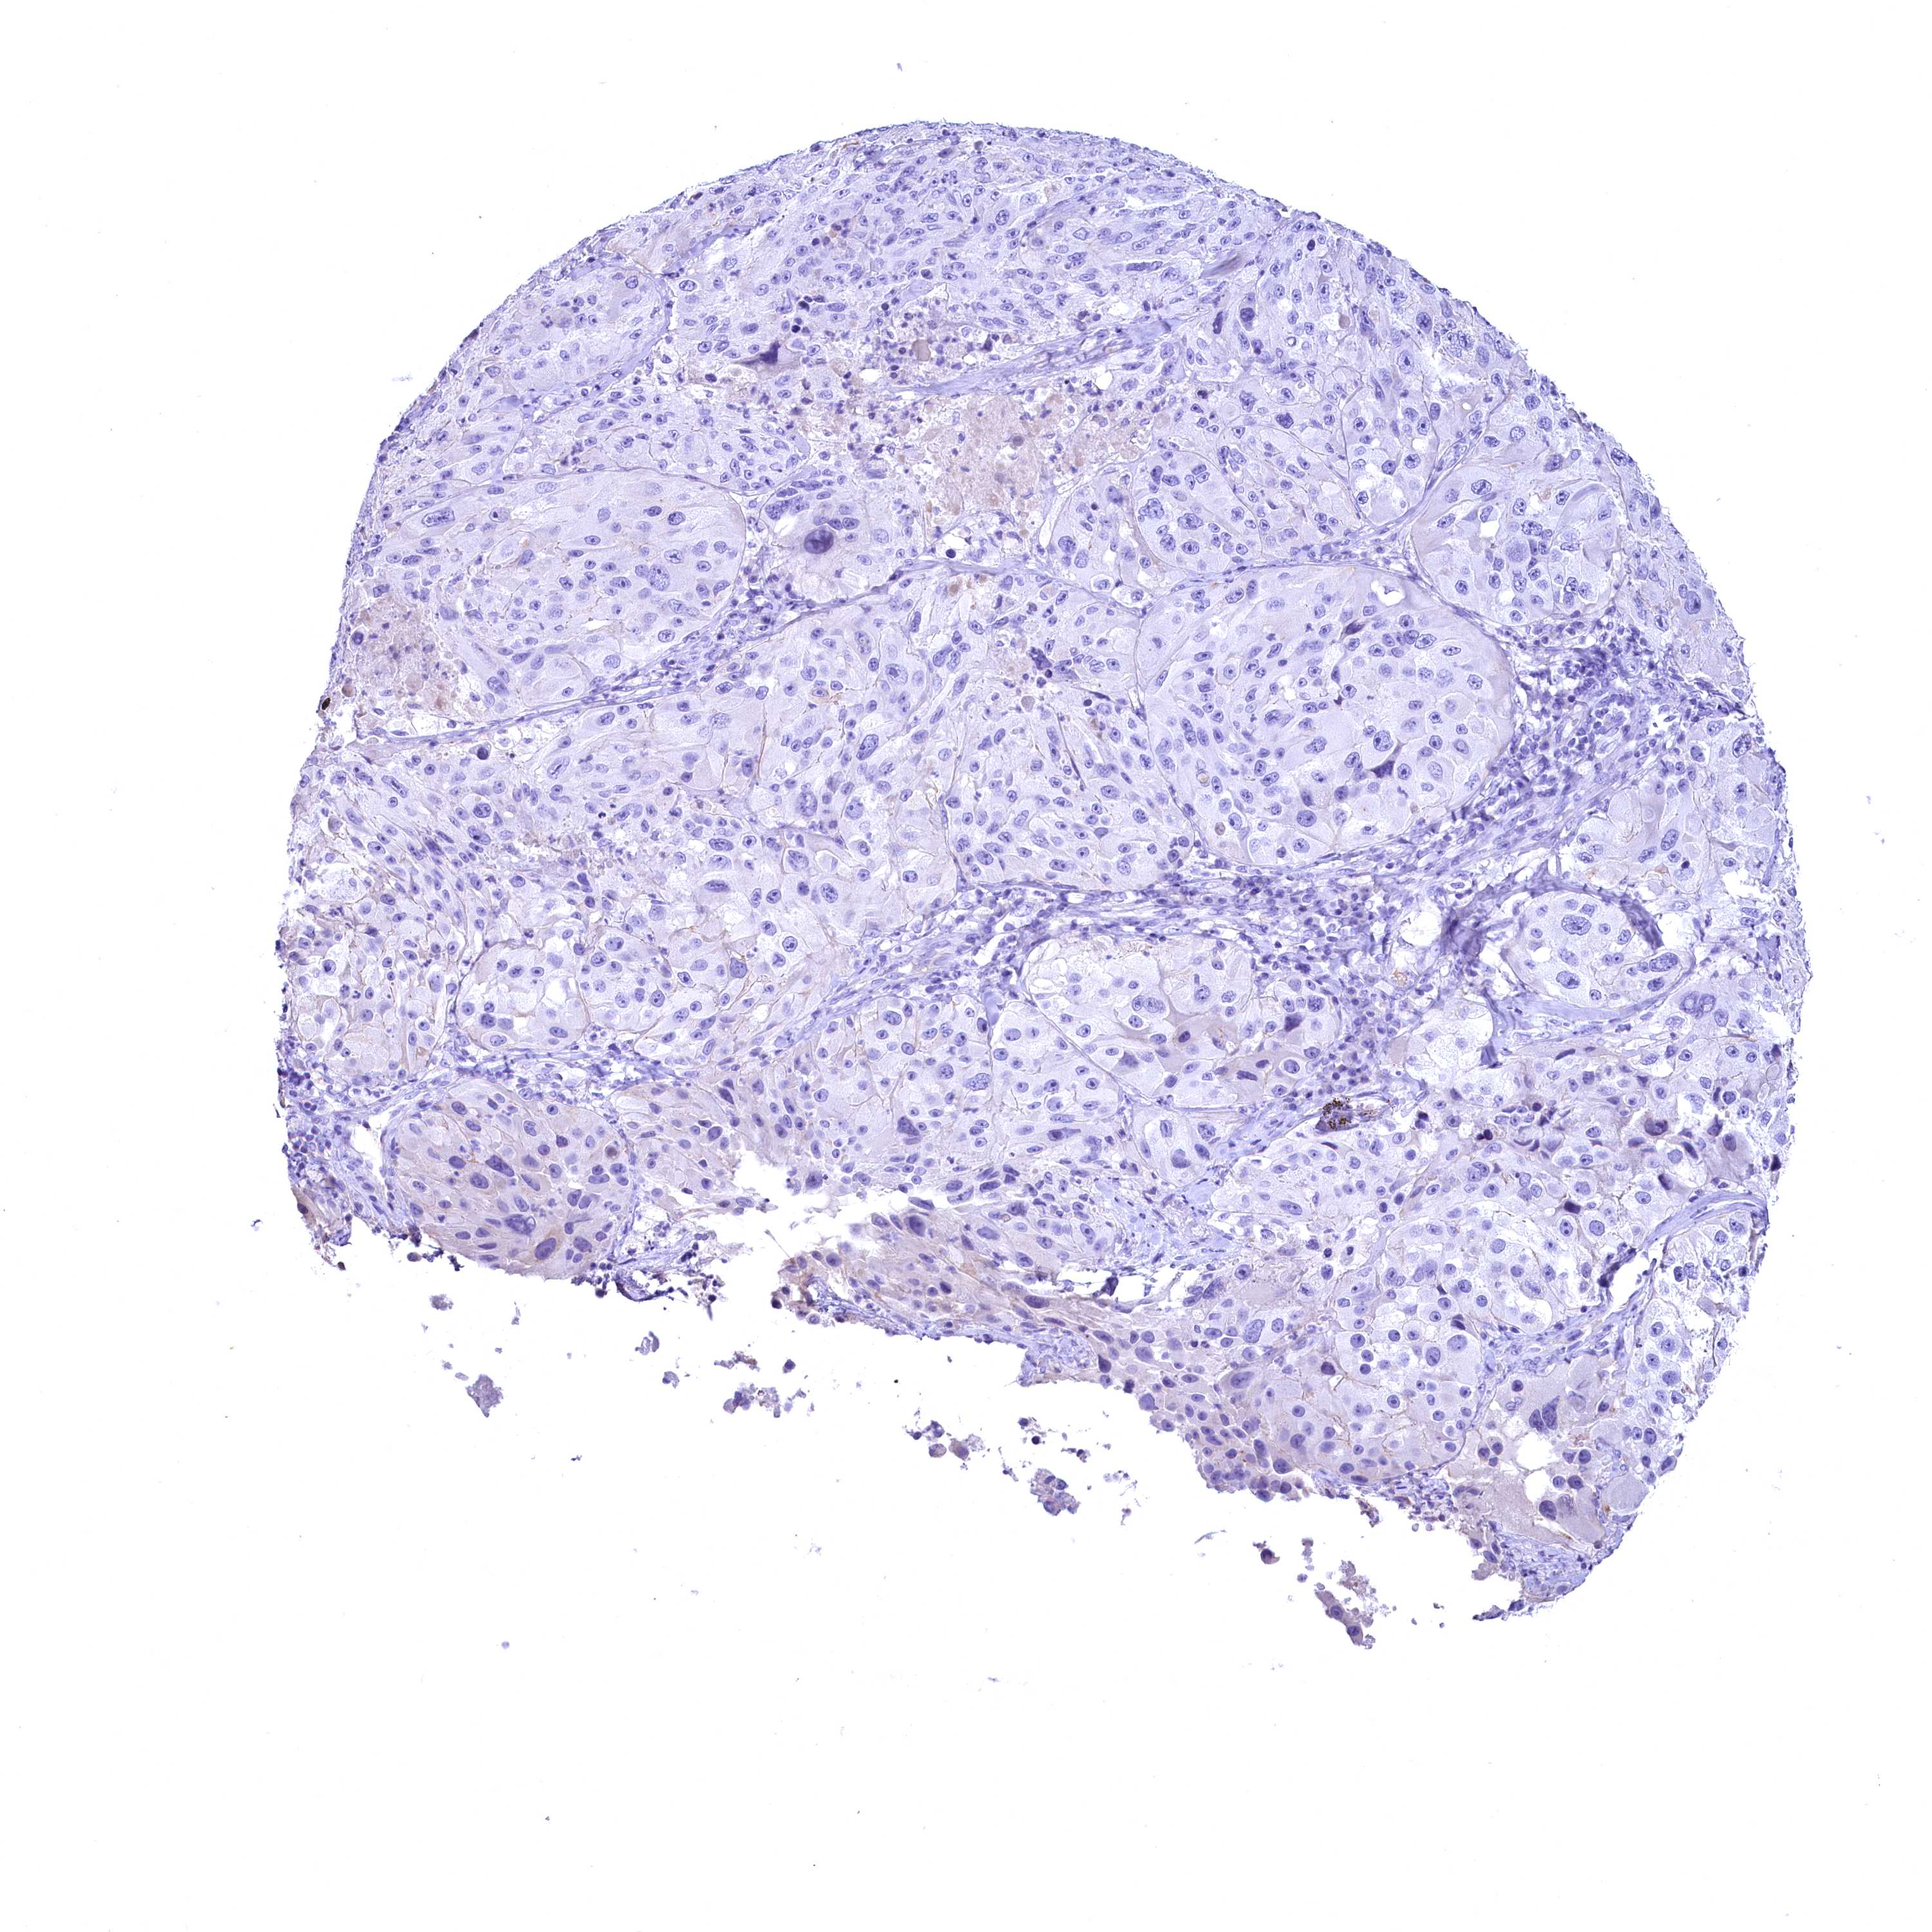

MELANOMA - Protein expressioni

A mouse-over function shows sample information and annotation data. Click on an image to view it in a full screen mode. Samples can be filtered based on level of antibody staining by selecting one or several of the following categories: high, medium, low and not detected. The assay and annotation is described here.

Note that samples used for immunohistochemistry by the Human Protein Atlas do not correspond to samples in the TCGA dataset.

Antibody stainingi

Antibody staining in the annotated cell types in the current human tissue is reported as not detected, low, medium, or high, based on conventional immunohistochemistry profiling in selected tissues. This score is based on the combination of the staining intensity and fraction of stained cells.

Each image is clickable and will lead to virtual microscopy that enables deeper exploration of all samples and also displays staining intensity scores, fraction scores and subcellular localization as well as patient and tissue information for each sample.

Antibody HPA039208

Antibody HPA040439

Staining

High

Medium

Low

Not detected

Intensity

Strong

Moderate

Weak

Negative

Quantity

>75%

75%-25%

<25%

None

Location

Nuclear

Cytoplasmic/membranous

Cytoplasmic/membranous,nuclear

Malignant melanoma, NOS

Malignant melanoma, Metastatic site